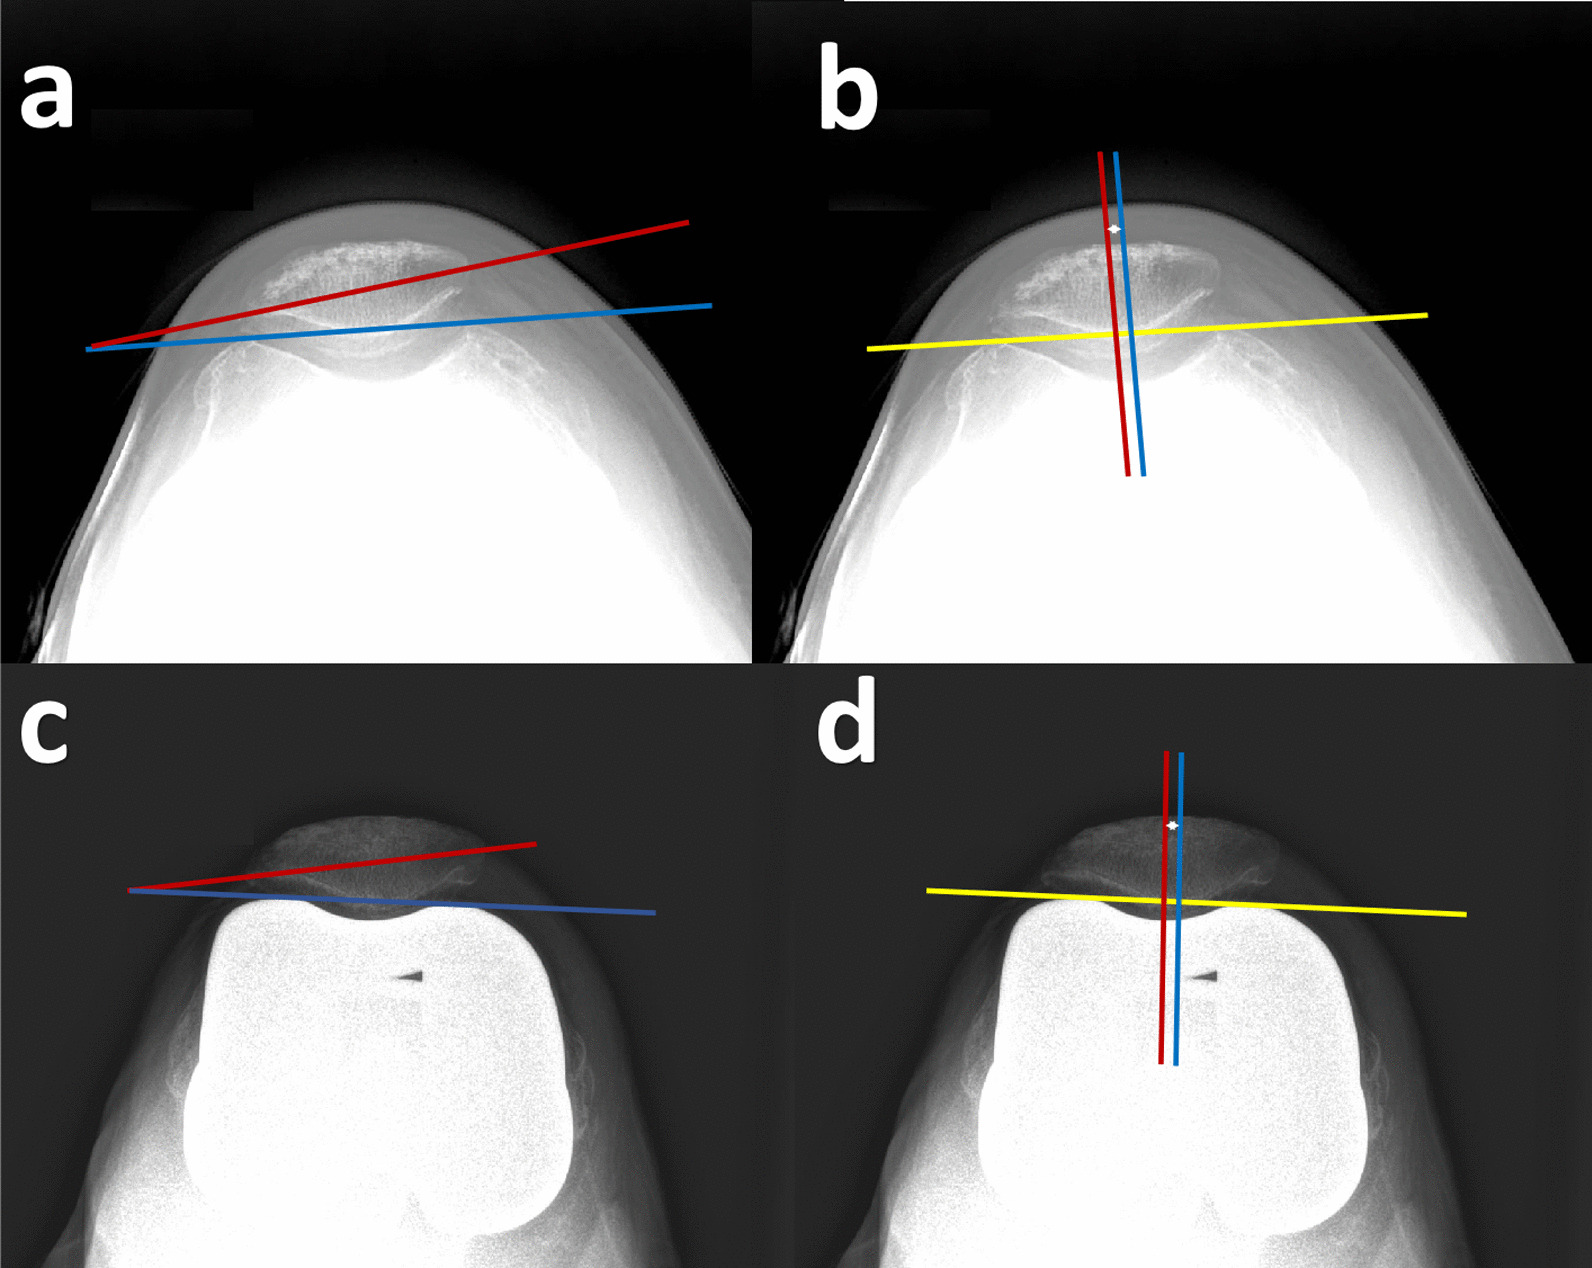

Fig. 2.

Measurements of preoperative and postoperative patellar tracking. a, c Preoperative and postoperative patellar tilt: angle between the line through the two anterior femoral condyles (blue line) and the patellar equator line (red line). b, d Preoperative and postoperative patellar displacement: the line through the anterior condyle of the femur was used as the baseline (yellow line), and the perpendicular lines (red and blue lines) were made from the baseline through the lowest point of the trochlea and the patellar ridge, respectively, and the distance between the two lines was measured